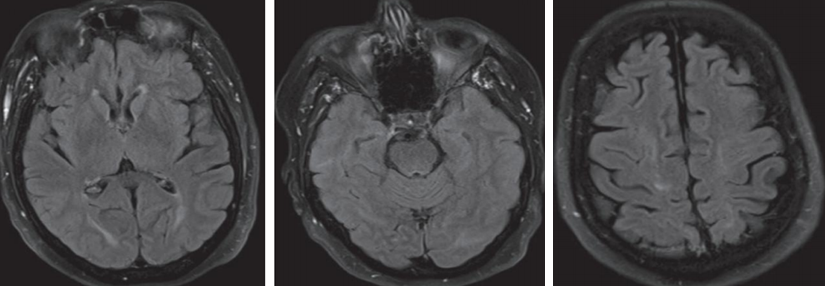

病例12

61岁男患,癫痫。2014年头MRI如下:

2020年头MRI如下:

答案:脑淀粉样血管病相关炎症(CAA-RI)。多呈急性或亚急性起病,最常见的表现是认知及行为改变,可表现为不同程度的痴呆、幻觉、人格改变、意识障碍甚至昏迷,其次是偏瘫、偏身感觉障碍、失语、共济失调等局灶性神经功能受损表现。另外,以癫痫、头痛等症状起病的患者亦不在少数,而相比单纯CAA而言,颅内出血的发生率则较低。MRI上最常见的表现为软脑膜明显强化及T2WI或FLAIR上的皮质下白质高信号灶,病灶常为非对称性,可散在分布或融合成片,灰质较少累及。